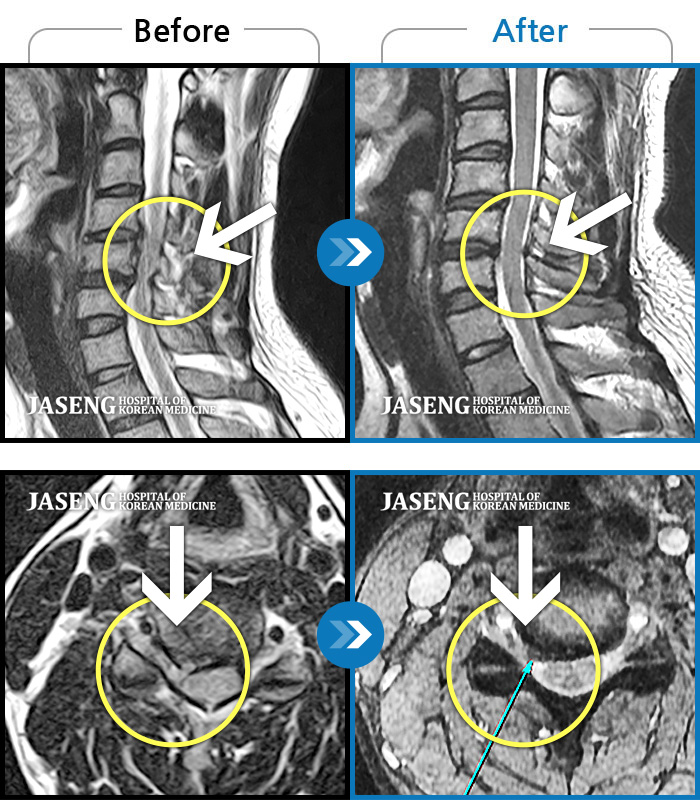

목디스크

부천 · 신동재 원장

목과 왼쪽 팔에서 1,2번째 손가락까지 저리고 당기는 통증

촬영시기

2012.05.07 ~ 2013.03.13

2013.03.27